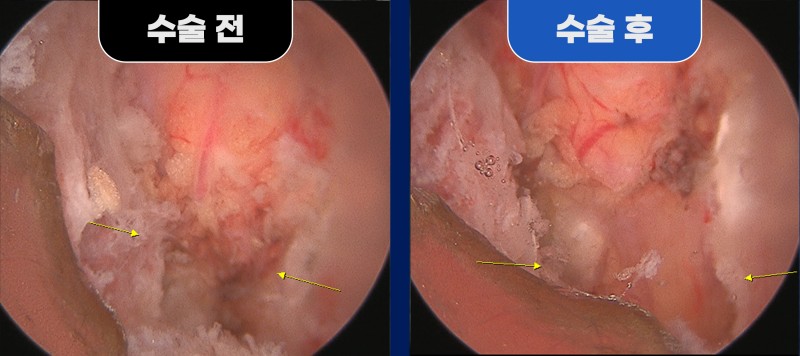

환자분은 양방향 척추 내시경 수술로 치료를 진행하였습니다.

좌측 요추 5번/천추 1번 추간공 확장술과 함께 횡돌기와 천추 날개뼈 사이의 가관절을 제거하고,

신경 주행을 압박하던 구조물을 충분히 감압하였습니다.